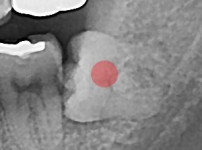

部分埋伏智齿